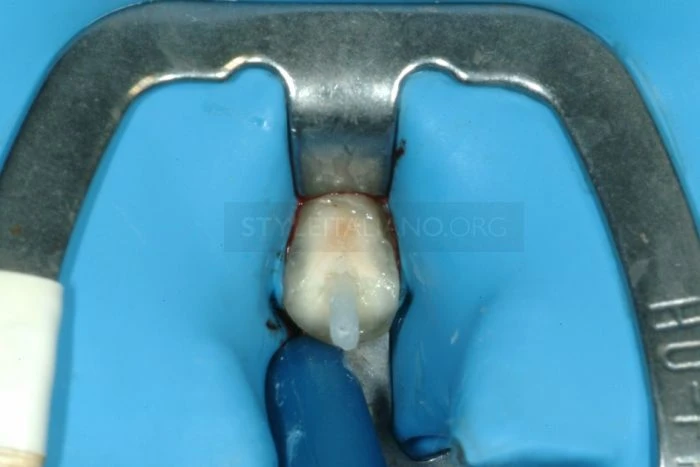

Đây là thời điểm để đặt tấm cao su cách ly.

Trước khi gắn răng vào đúng vị trí cần phải điều trị để giảm số lượng vi khuẩn đặc biệt trong trường hợp này vì vị trí gắn sẽ được phủ bởi vạt: kết quả là răng đã được cách ly, không cần khâu dưới vạt, với tấm cao su cách ly đã được rửa sạch bằng 0,2% Chlorexidine (Curaden – Curasept 0,20% + Ialuronic Acid).

Sau khi đặt tấm cao su cách ly với kẹp, tiến hành điều trị tủy và tạo khoảng đặt chốt.